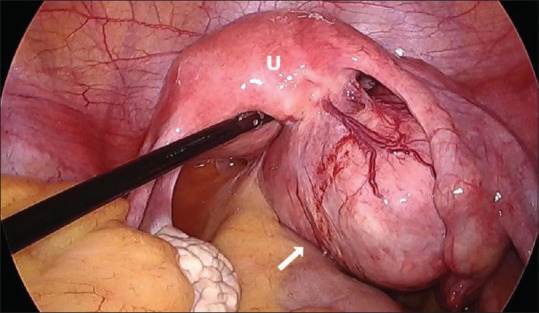

We report a case of a pedunculated adenomyoma with osseous metaplasia, which mimics a dermoid cyst on magnetic resonance imaging (MRI) making it a considerable differential diagnosis. A 40-year-old female presented with chronic lower abdomen pain for a year. Pelvic MRI revealed a right-sided pelvic mass measuring 8.4 cm × 5.7 cm. The mass appeared isointense, with hyperintense contents similar to calcifications and fatty content. These results strongly indicated a dermoid cyst. During laparoscopy, a massive pedunculated uterine myoma was seen on the right posterior-fundal part of the uterus. During laparoscopic myomectomy, calcified tissues were discovered during manual morcellation. The histopathological examination confirmed the diagnosis of adenomyoma with widespread calcification and localized osseous metaplasia. Osseous metaplasia is an uncommon cytomorphological transformation seen mostly in the endometrium. Adenomyomas are rare, benign uterine tumors that are frequently misdiagnosed. In this case, the preoperative diagnosis suggested a dermoid cyst, broadening the differential diagnosis for calcified uterine tumors detected on MRI.